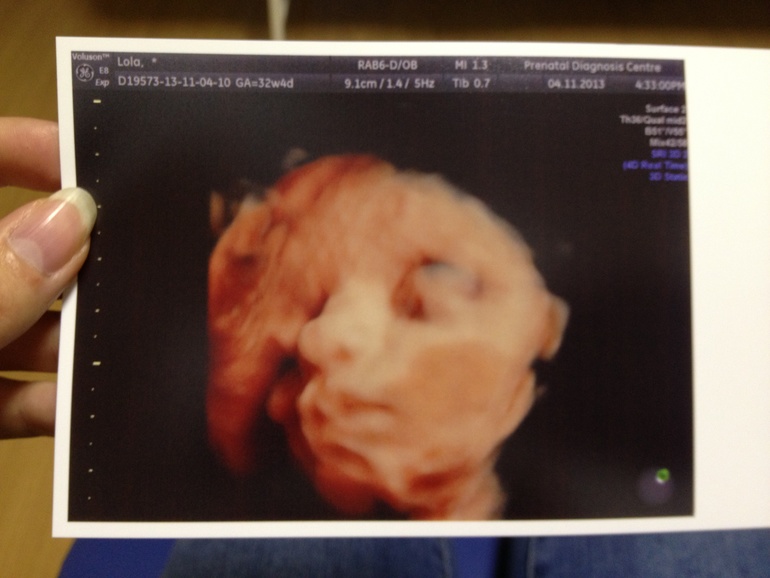

УЗИ 32 недели + 4 дня

ИТАК. Набираем вес мы хорошо, сегодня мы весим 1679 грамм (за 3 недели + 569 грамм). По прежнему худенький животик, но зато щечки она отъела как хомячок =)))

И, наконец, фото: